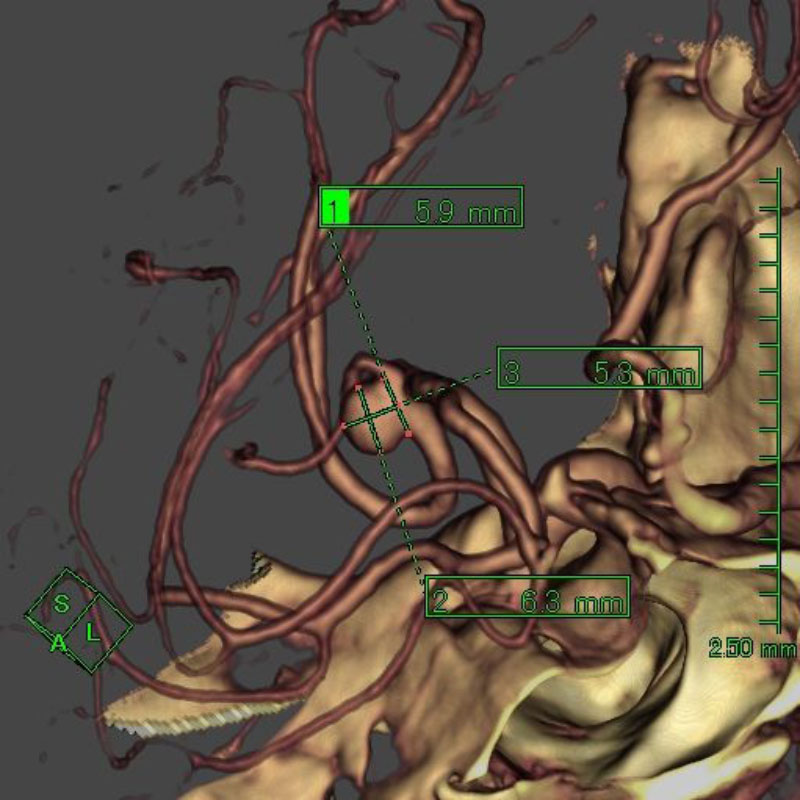

脳底動脈瘤

クリッピング術

手術前

クリップ前

クリップ後